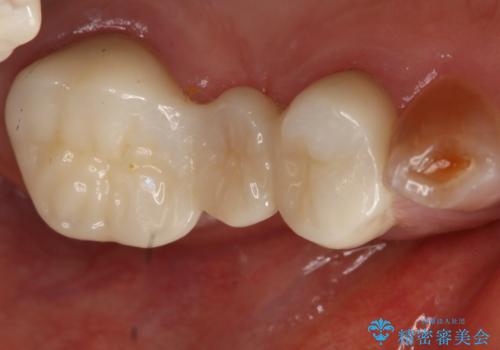

- 297,000円(フルジルコニアクラウン、仮歯それぞれ3本分)費用は治療当時の料金となります

露髄や痛みなどの症状も出ず、経過は良好です。